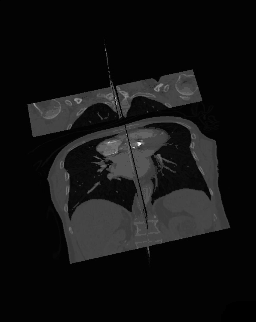

• 3D Multi-Planar Reconstruction

A final variant on the MPR theme is the generation of a three-dimensional display showing all three orthogonal projections combined so that a defined point of interest locates the intersection of the planes, as illustrated in the following figure:

3D Orthogonal MPR rotating sequence.

The point of intersection is located for illustrative purposes at the centre of the voxel data in the figure above. It can typically be placed at any point in the 3D data using interactive controls. In addition, the perspective used for the rotating sequence can typically be manipulated interactively to improve the visualization of a region of interest. Note that the image sequence illustrated above is one from a myriad of perspectives that can thus be generated. Note also that slice projections (e.g. MIPs) can be combined with this form of display to provide additional perspectives on a feature of interest.